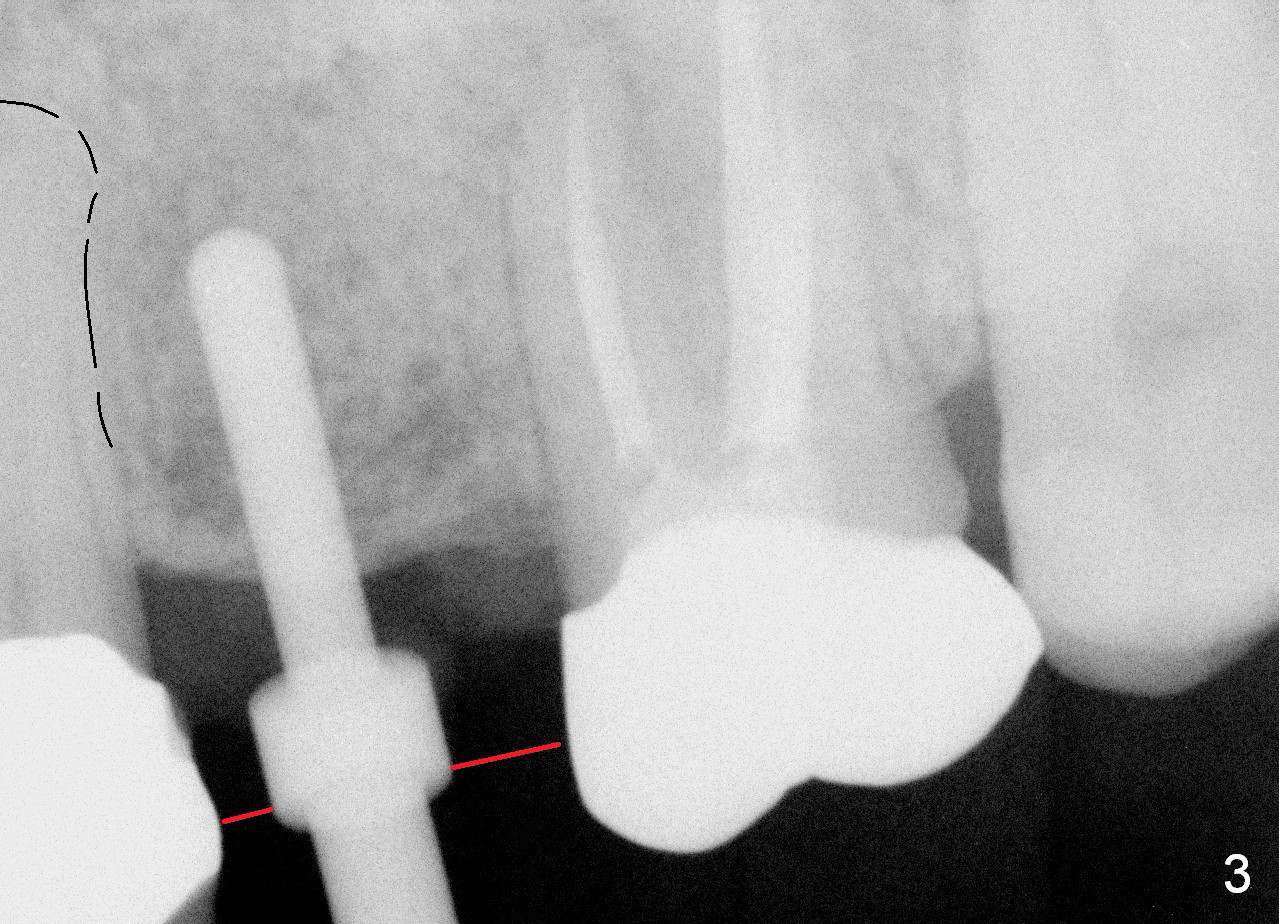

A 45-year-old lady is nervous about dental treatment. The missing tooth #13 was replaced by a 3-unit bridge. The latter is sectioned because the posterior abutment has caries. PA in Fig.1 is taken when root canal therapy and build up are finished. Fig.2 shows the wide edentulous area with a single-unit crown being tried in for #14. Osteotomy is initiated with the crown in place without cementation, since it is easy to determine the mesiodistal position (Fig.3 red lines). Without the crown in place, osteotomy tends to be distal. In this case, the osteotomy is later attempted to be moved distally with Lindamann bur and deepened to 14 mm from the gingival margin (Fig.4). A 2.5 mm reamer is being used at 50 RPM to increase osteotomy with difficulty. Drills have to used at high RPM instead (Fig.5 4x14 mm). A 4.5x14 mm tissue-level implant is placed with insertion torque >60 Ncm (Fig.6 I); a 4x3 mm abutment (A) is placed immediately for an immediate provisional. Fig.7 is taken 7 days postop to show the gingival recipient site formed by the provisional. The patient is so afraid of X-ray that the next one is taken 1.5 years post cementation (Fig.8). It appears that dense bone bundle forms between the crest and the 1st implant thread (adaptation functional change, arrowheads). The bone density continues to increase 2 years 8 months post cementation (Fig.9 *, 10); the bone has grown into the area between the 1st 2 threads (arrow).